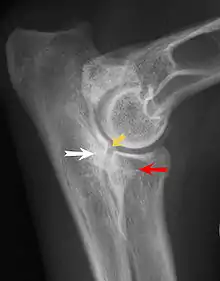

Ununited anconeal process

Most primary lesions are related to osteochondrosis, a disease of the joint cartilage, and osteochondritis dissecans (OCD), the separation of a flap of cartilage on the joint surface. Other common causes of elbow dysplasia include an ununited anconeal process (UAP) and fragmented or ununited medial coronoid process (FCP or FMCP).[1]

In OCD, the normal change of cartilage to bone in the development of the joint fails or is delayed. The cartilage continues to grow and may split or become necrotic. The cause is uncertain, but possibly includes genetics, trauma, and nutrition (including excessive calcium and decreased vitamin C intake).[4] OCD lesions found in the elbow at the medial epicondyle of the humerus are caused by disturbed endochondral fusion of the epiphysis of the medial epicondyle with the distal end of the humerus, which may in turn be caused by avulsion of the epiphysis.[5] Specific conditions related to OCD include fragmentation of the medial coronoid process of the ulna (FMCP) and an ununited anconeal process of the ulna (UAP). All types of OCD of the elbow are most typically found in large breed dogs, with symptoms starting between the ages of 4 and 8 months.[4] Males are affected twice as often as females. The disease often affects both elbows (30 to 70 percent of the time), and symptoms include intermittent lameness, joint swelling, and external rotation and abduction of the paw.[6] Osteoarthritis will develop later in most cases.

UAP is caused by a separation from the ulna of the ossification center of the anconeal process.[7] FMCP is caused by a failure of the coronoid process to unite with the ulna.